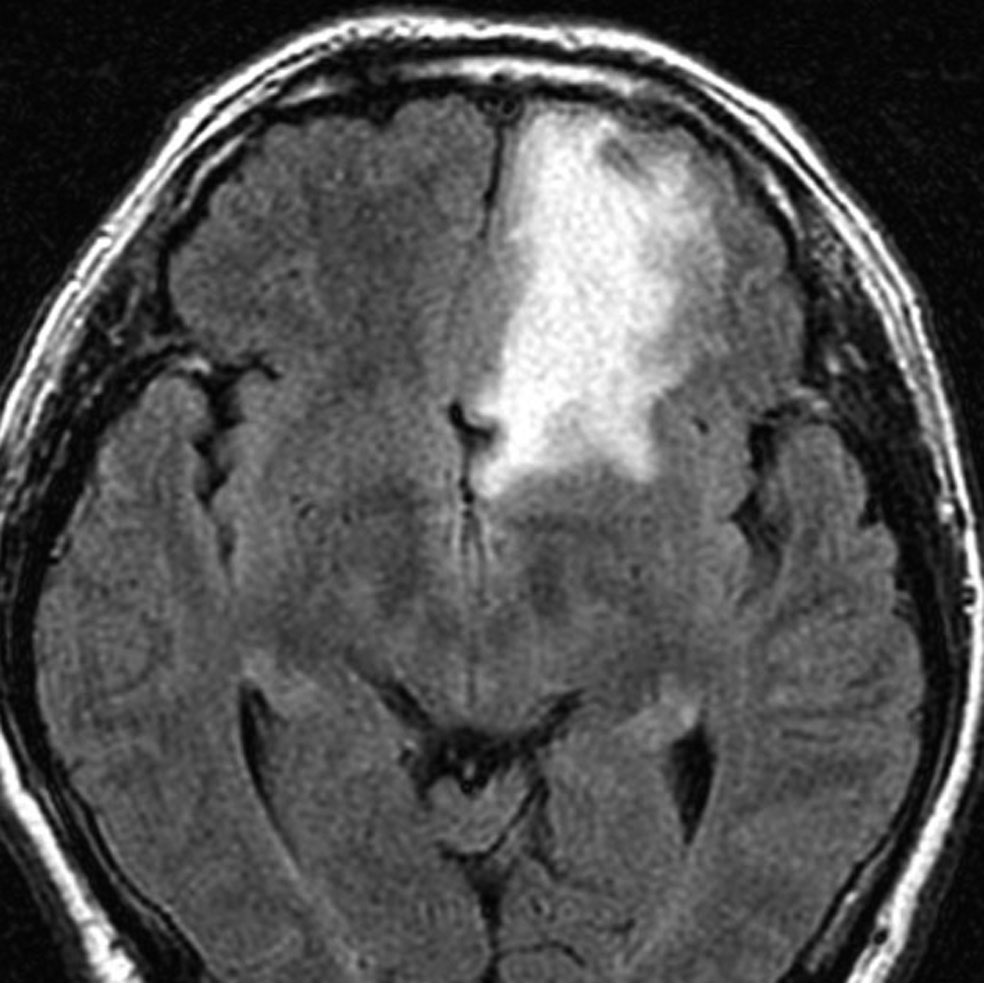

- T2強調やフレア画像では,腫瘍周囲に強い脳浮腫(脳が腫れる)があることも多いです

左は,造影剤を使ったガドリニウム増強MRIです。腫瘍が白く丸く見えます。右はフレア画像で,腫瘍の周囲の脳浮腫(脳のはれ)です。左前頭葉が,かなり強くはれています。この腫瘍は小さいのですが,脳のはれが強すぎるので手術摘出したほうがいいです。浮腫が悪化すると,てんかん発作や認知機能低下がでる可能性があります。

- 周辺の脳が腫れている脳浮腫がめだつ時は,症状がなくても手術で摘出した方がいいこともあります

脳浮腫(脳のはれ)

- 髄膜腫が発見されると「まわりの脳が腫れている」と説明されることがあります

- これを腫瘍周辺脳浮腫 peritumoral brain edema といいます

- 髄膜腫の20-30%くらいでみられます

- 脳浮腫が強いと,はれている部分の脳の機能が落ちます

- 認知症,感覚障害,運動麻痺,失語症,てんかん発作などの症状が出やすくなります

- 髄膜腫が全部とれると,この脳の腫れも消えます

- 腫瘍血管が増える時にVEGFが産生されるために,脳の細血管の透過性が亢進して,血液の中の血漿成分が脳組織の中に漏れ出ることが原因です